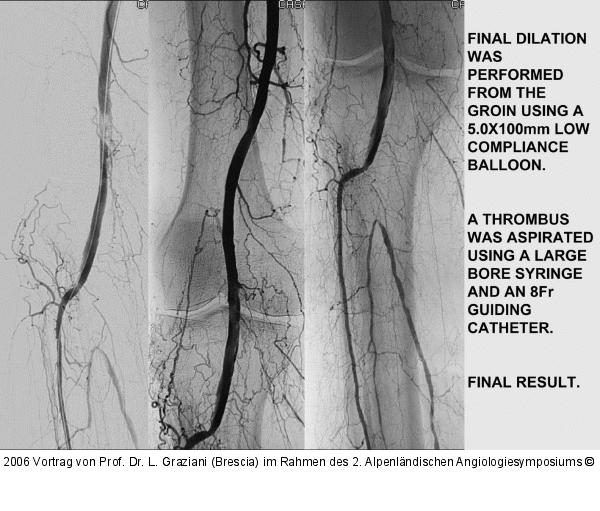

Vortrag von Prof. Dr. L. Graziani (Brescia) im Rahmen des 2. Alpenländischen Angiologiesymposiums

PTA of the foot arteries in diabetics: Extremities Extreme Angioplasty

Abbildung 67: P.O.B.A.